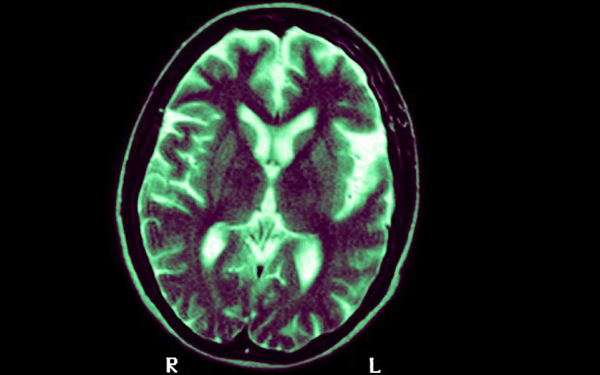

Ha évtizedekkel a betegség kezdete előtt, negyvenévesen beadják a vakcinát, akkor a kutatók szerint azokat a lerakódásokat takaríthatja ki az agyból, amelyek blokkolják az agyi elektromos jeladást – idézte a The Daily Telegraph a Cheltenham Science Festivalon elhangzott előadást.

James Nicoll, a Southamptoni Egyetem ideggyógyásza azt fedezte fel, hogy egy védőoldás beindíthatja az immunrendszert, amely eltávolítja az agyi lerakódásokat. A vakcina ugyanabból az amiloid béta fehérjéből készül, ami az Alzheimer-kóros betegek agyában felhalmozódik.

Nicoll elmondta: a betegek agyából az oltás eltávolította a lerakódásokat, ám nem állította meg a mentális hanyatlást és nem akadályozta meg a korai halált. Ennek ellenére úgy véli, ha 40-50 éves koruk között kapják meg az emberek a védőoltást, amikor a betegségnek még semmi jele nincs, az megelőzheti, hogy a lerakódások kialakulásuk elkezdődjön.